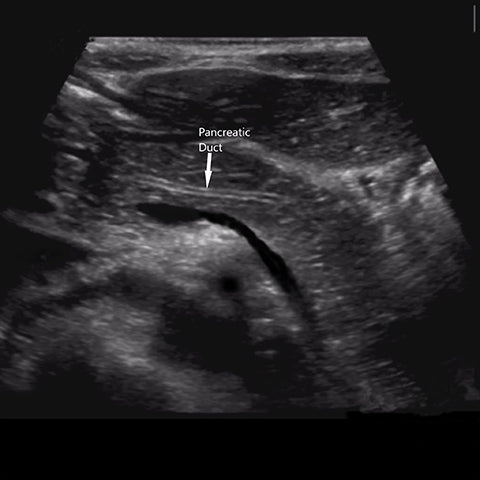

Today we are thankful for clearly visualized pancreas .We can give you visual instruction.